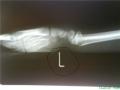

dr_MG Опубликовано: 18 февраля, 2008 Жалоба Share Опубликовано: 18 февраля, 2008 (изменено) Продолжим 1.Рентгеновский снимок. Кое-что выделено. Вопрос: что это и как это туда попало? 2.Что за болезнь изобразил художник. 3.Дядька с зажимом в руках рекламирует метод лечения глаукомы. Кое-что на картинке подчищено. В качестве подсказки скажу, что этот "девайс" распространен и поныне, но не в медицине.. Изменено 19 февраля, 2008 пользователем Zhuk Исправил последовательность картинок в соответствии с вопросами. Цитата Kişinin sözü beer olar. Ссылка на комментарий Поделиться на других сайтах More sharing options...

dr_MG Опубликовано: 18 февраля, 2008 Жалоба Share Опубликовано: 18 февраля, 2008 Рентген - да, пальца - нет. Артефакт действительно гвоздь, только как он попал на снимок? Версия про ладонь неверна. 3 - все нет. Цитата Kişinin sözü beer olar. Ссылка на комментарий Поделиться на других сайтах More sharing options...

Monro Опубликовано: 18 февраля, 2008 Жалоба Share Опубликовано: 18 февраля, 2008 а это вообще человеческий снимок? похоже на крыло птицы или плавник тюленя... Цитата Ссылка на комментарий Поделиться на других сайтах More sharing options...

dr_MG Опубликовано: 18 февраля, 2008 Жалоба Share Опубликовано: 18 февраля, 2008 Человеческий Цитата Kişinin sözü beer olar. Ссылка на комментарий Поделиться на других сайтах More sharing options...

elMarlboro Опубликовано: 18 февраля, 2008 Жалоба Share Опубликовано: 18 февраля, 2008 гвоздь кажется вбит в сам лежак и никакого отношения к пациенту не имеет Цитата куплю машину времени......возможен бартер ;) Ссылка на комментарий Поделиться на других сайтах More sharing options...

Naila_doc Опубликовано: 19 февраля, 2008 Автор Жалоба Share Опубликовано: 19 февраля, 2008 На первый вопрос я уже давно знаю ответ))) Нет, не в лежак он вбит) Цитата Воздух не чувствуется, пока его не испортят. Ссылка на комментарий Поделиться на других сайтах More sharing options...

elMarlboro Опубликовано: 19 февраля, 2008 Жалоба Share Опубликовано: 19 февраля, 2008 тогда в объектив рентгеновского аппарата Цитата куплю машину времени......возможен бартер ;) Ссылка на комментарий Поделиться на других сайтах More sharing options...

lobbist Опубликовано: 19 февраля, 2008 Жалоба Share Опубликовано: 19 февраля, 2008 можт он у него в кармане)) Цитата Однажды я проснулся гением... всех времен и народов.. такой дудук нам не нужен. Ссылка на комментарий Поделиться на других сайтах More sharing options...

dr_MG Опубликовано: 20 февраля, 2008 Жалоба Share Опубликовано: 20 февраля, 2008 Дядька действительно рекламирует марихуану как метод лечения глаукомы. Зверь на ноге - подагра. Остался рентген... Гвоздь вбит не в лежак и не объектви аппарата. И не в кармане он. Обратите внимание на сам снимок. Что там изображено и все ли в порядке с тем, что снимали? Цитата Kişinin sözü beer olar. Ссылка на комментарий Поделиться на других сайтах More sharing options...

elMarlboro Опубликовано: 20 февраля, 2008 Жалоба Share Опубликовано: 20 февраля, 2008 протез может...пальца Цитата куплю машину времени......возможен бартер ;) Ссылка на комментарий Поделиться на других сайтах More sharing options...

lobbist Опубликовано: 20 февраля, 2008 Жалоба Share Опубликовано: 20 февраля, 2008 нога или рука сломана?) Цитата Однажды я проснулся гением... всех времен и народов.. такой дудук нам не нужен. Ссылка на комментарий Поделиться на других сайтах More sharing options...

Danaja Опубликовано: 20 февраля, 2008 Жалоба Share Опубликовано: 20 февраля, 2008 Лоббист естественно рука )) кисть, запястье где гвоздь и лучевая кость . ИМХО )))) может подложена какая нить доска вместо шины , что под руку попалось , а в ней гвоздь ??? Если Naila_doc говорит - "лежак без гвоздей ", то других догадок у меня нет . Цитата Ссылка на комментарий Поделиться на других сайтах More sharing options...

dr_MG Опубликовано: 21 февраля, 2008 Жалоба Share Опубликовано: 21 февраля, 2008 Даная, все верно! На снимке перелом, поставили шину из подручных средств. Попалась доска с гвоздем)) Цитата Kişinin sözü beer olar. Ссылка на комментарий Поделиться на других сайтах More sharing options...